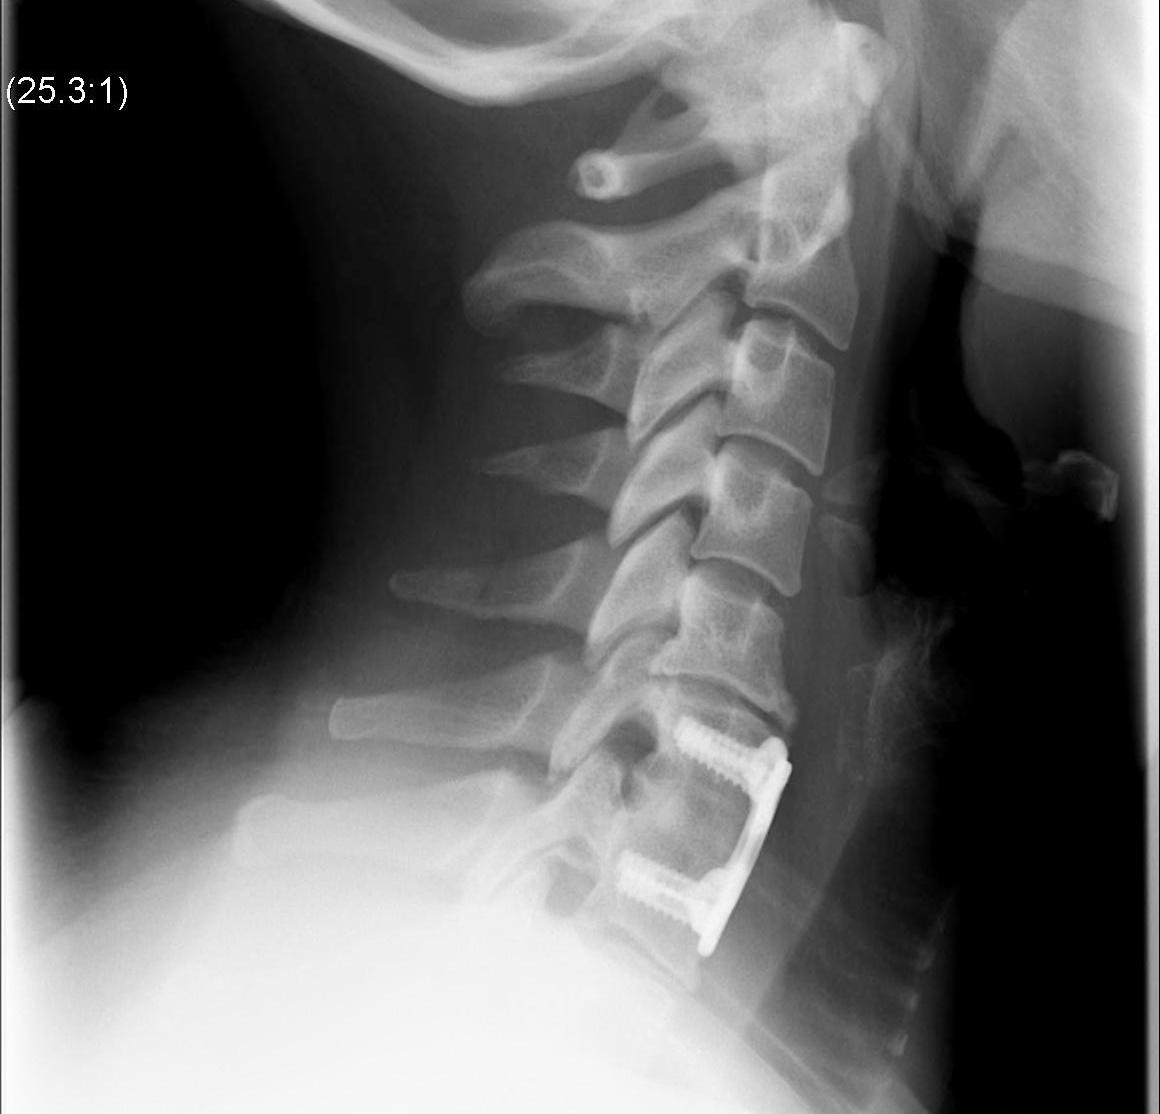

ACDF / Fusion

Technique

Anterior approach / Smith Robinson

- discectomy

- decorticate end plates

- interbody fusion with bone graft +/- interbody spacer

- anterior plate / integrated cage